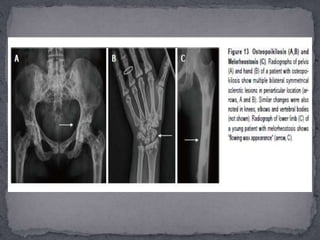

 It isa benign condition with autosomal dominant inheritance, more common in males characterised by multiple small (1-10 mm), symmetric, uniform radiopaque densities located at ends of long bones, carpals, tarsals and periacetabular and subglenoid areas.  An important differentialan be osteoblastic metastases which can be differentiated by the variable size of lesions and by radionuclide scintigraphy.

 Benign conditionwith a X-linked dominant inheritance.  It is more commonly seen in females and is characterised by bilateral symmetric involvement of long bones, pelvis and scapulae in the form of multiple vertical radio opaque lines in the metaphysis extending into the diaphysis. In the pelvis, this gives a sunburst effect. Other findings include osteosclerosis of long bones and skull leading to foraminal narrowing and cranial nerve compression.

 Melorheostosis canbe both a sporadic, non-inherited disorder or an inherited disorder presenting with melorheostosis and osteopoikilosis .  Melorheostosis is a benign condition characterised clinically by pain and soft-tissue contractures.  The distribution is asymmetric, can be monostotic (involving single bone) or polyostotic (involving multiple bones) or monomelic (involving one limb), most typically the lower limb.  Other bones like skull, ribs, spine and short tubular bones can be affected at times. There is typically cortical thickening in a streaky or wavy pattern extending from the proximal to distal part of bone giving a “flowing wax candle appearance”. The distribution in children is usually endosteal (which can mimic bone islands and osteopoikilosis) but this evolves to a periosteal pattern in adults.